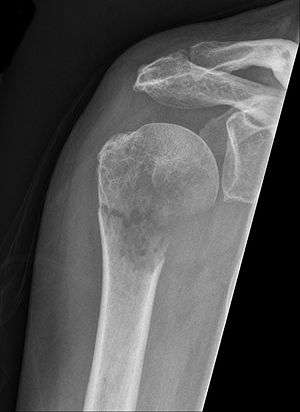

Pathological fracture of the humerus in a patient with metastasis of renal cell carcinoma

A pathologic fracture is a bone fracture caused by disease that led to weakness of the bone structure. This process is most commonly due to osteoporosis, but may also be due to other pathologies such as: cancer, infection, inherited bone disorders,or a bone cyst. Only a small number of conditions are commonly responsible for pathological fractures, including osteoporosis, osteomalacia, Paget's disease, osteitis, osteogenesis imperfecta, benign bone tumours and cysts, secondary malignant bone tumours and primary malignant bone tumours.[1]

Pathological fractures present as a chalkstick fracture in long bones, and appear as a transverse fractures nearly 90 degrees to the long axis of the bone. In a pathological compression fracture of a spinal vertebra fractures will commonly appear to collapse the entire body of vertebra.